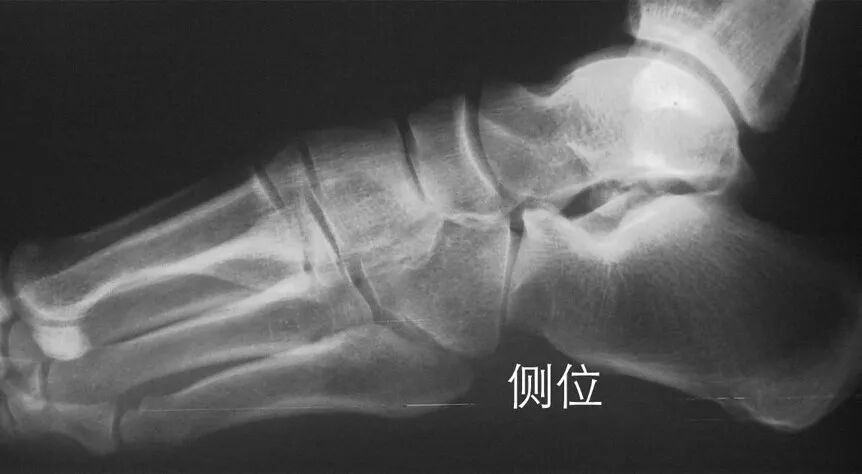

侧位上,跖骨不超过相应楔骨背侧缘。从远端的跖骨经过跖跗关节到近端的跗骨,应该是一条不间断的连线

2005年Pearse等提出“ABC”的方法来阅读足部X 线片, 以减少中、前足的漏诊。 A ( alignment)检查跖骨与相应楔骨的对应线 B ( bone)检查每一块骨的轮廓 C ( congruity )检查整体一致吻合, 在正位片上观察内柱, 在斜位片上观察中、外柱。侧位片的常规检查可发现Lisfranc关节矢状面的半脱位及撕脱性骨折